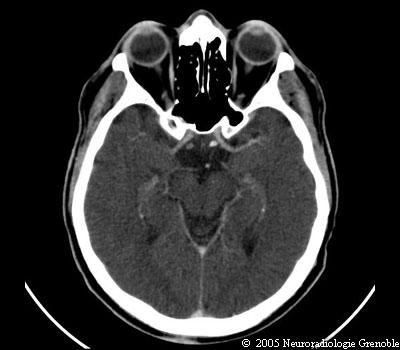

Radioanatomie TDM de l'encéphale

TDM cérébrale sans injection